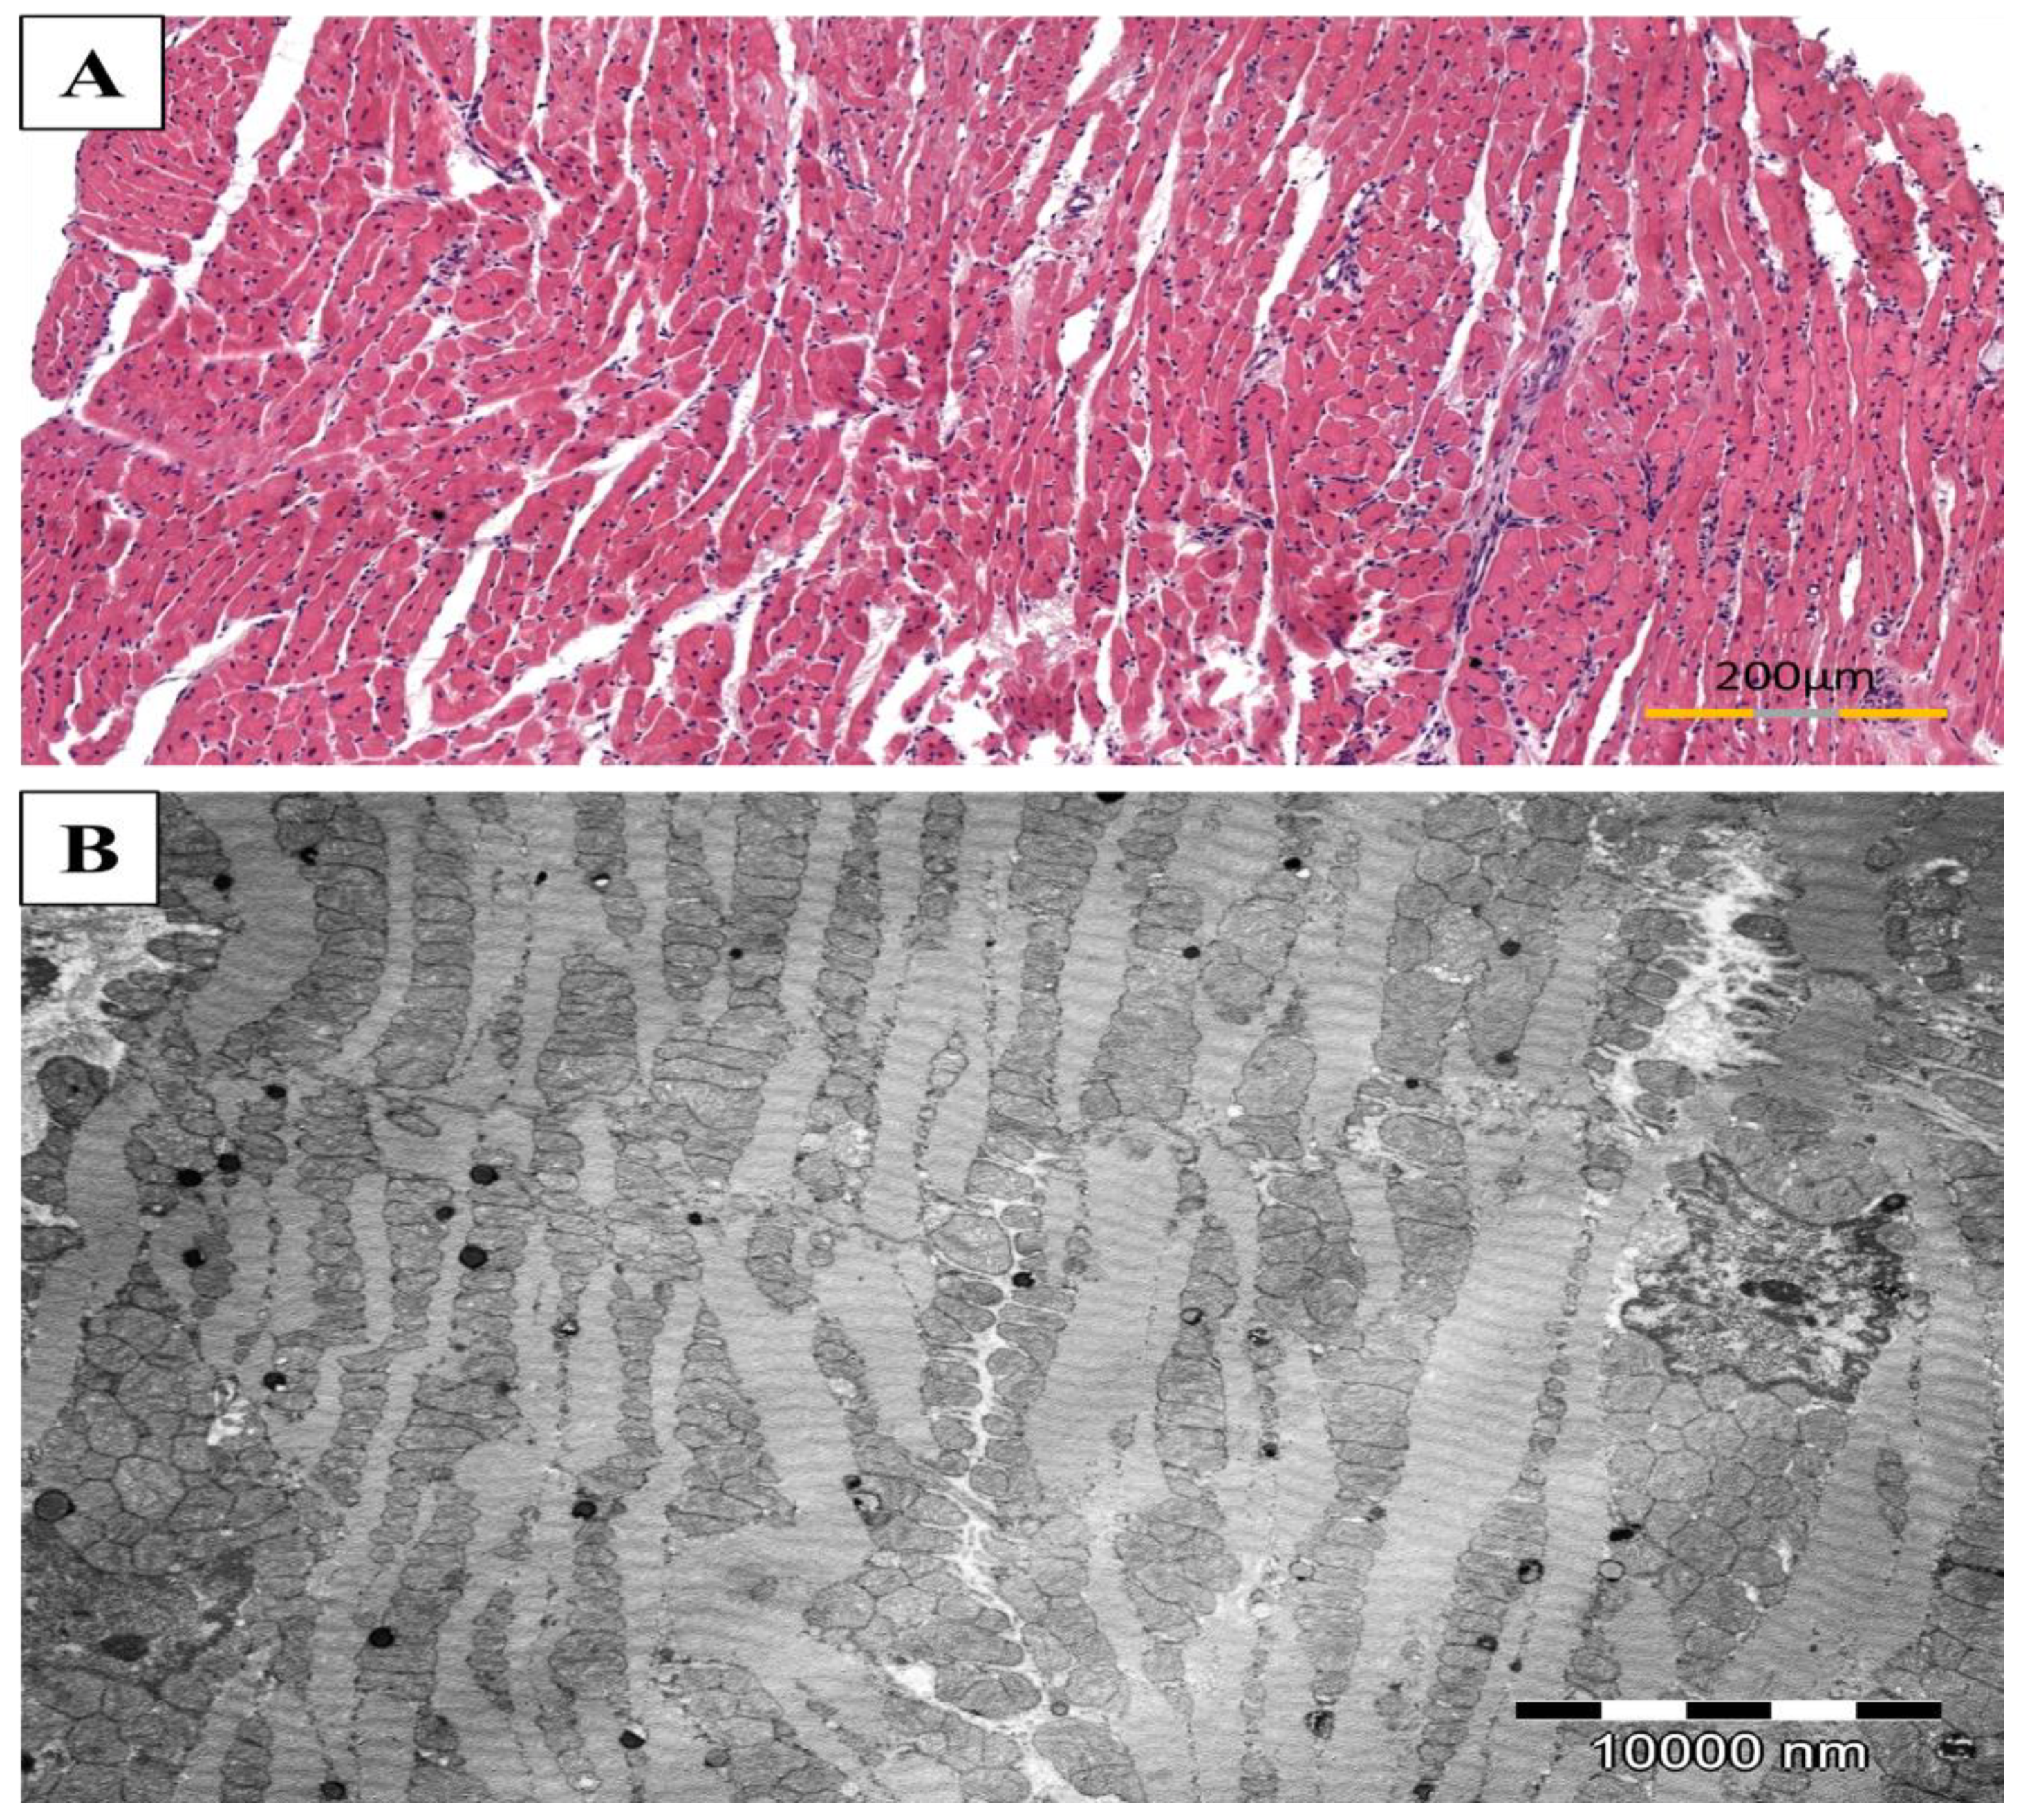

2.7. Assessment of the Severity of the Inflammation in the Light Microscope (HE)

2.8. Assessment of the Myofibrils in the Transmission Electron Microscope (TEM)

3.5. Reduction of the Severity of Inflammation by Simvastatin in Rat Heart Subjected to EAM

3.6. Protection of Myofibrils Degradation by Simvastatin in Rat Hearts Subjected to EAM